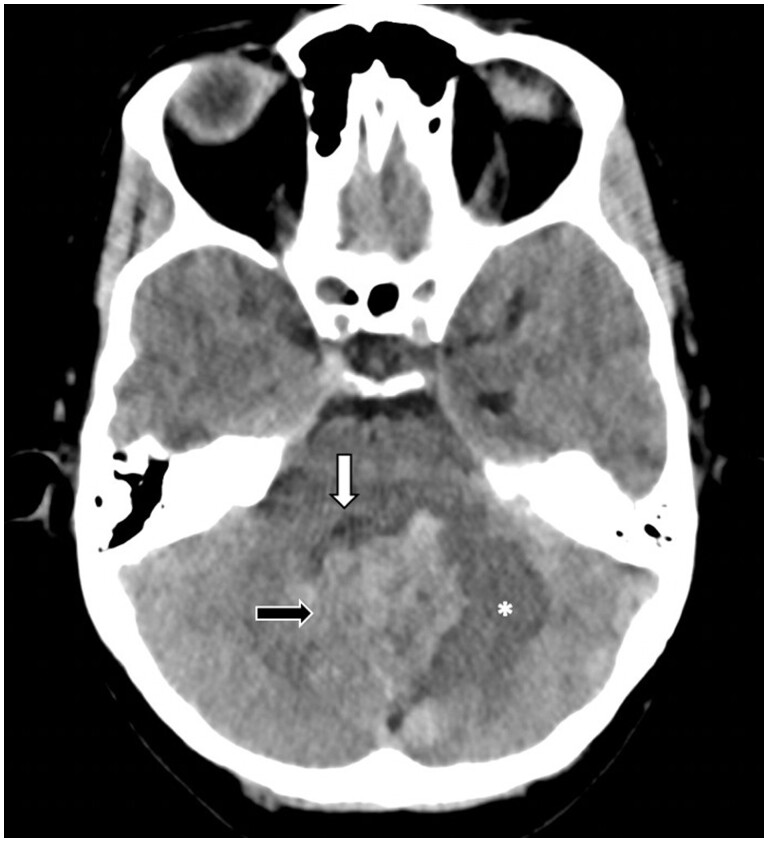

Optic nerve haemangioblastoma (ONH) is an uncommon, benign, non-meningothelial, mesenchymal tumour of unclear origin. Most are associated with von Hippel-Lindau (VHL) syndrome (71%), and only 40 cases have been reported in the medical literature. Most of the patients develop non-specific visual symptoms, including decreased visual acuity and/or loss of visual fields, exophthalmos, trigeminal neuralgia, and retroorbital pain. Optic nerve sheath meningioma and optic nerve glioma are among the differential diagnoses that may be considered in this location. Contrast-enhanced MRI is considered an optimal diagnostic tool, which helps to determine some characteristics that guide towards an adequate diagnosis and treatment. We present a 42-year-old patient with a history of VHL syndrome in whom a cerebellar lesion and optic nerve lesions were evidenced, and we did a review of the literature and case analysis.